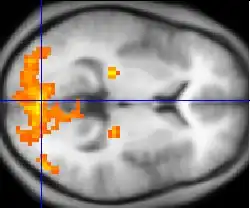

Hemodynamic

Hemodynamic techniques take advantage of the fact that when an area of the brain works at a task, blood is sent to supply that area with oxygen (in what is known as the Blood Oxygen Level-Dependent, or BOLD, response).[30] Such techniques include PET and fMRI. These techniques provide high spatial resolution, allowing researchers to pinpoint the location of activity within the brain;[2] temporal resolution (or information about the timing of brain activity), on the other hand, is poor, since the BOLD response happens much more slowly than language processing.[11][31] In addition to demonstrating which parts of the brain may subserve specific language tasks or computations,[20][25] hemodynamic methods have also been used to demonstrate how the structure of the brain's language architecture and the distribution of language-related activation may change over time, as a function of linguistic exposure.[22][28]

In addition to PET and fMRI, which show which areas of the brain are activated by certain tasks, researchers also use diffusion tensor imaging (DTI), which shows the neural pathways that connect different brain areas,[32] thus providing insight into how different areas interact. Functional near-infrared spectroscopy (fNIRS) is another hemodynamic method used in language tasks.[33]